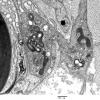

PERIPHERAL NEUROPATHY

7B CIDP (2)